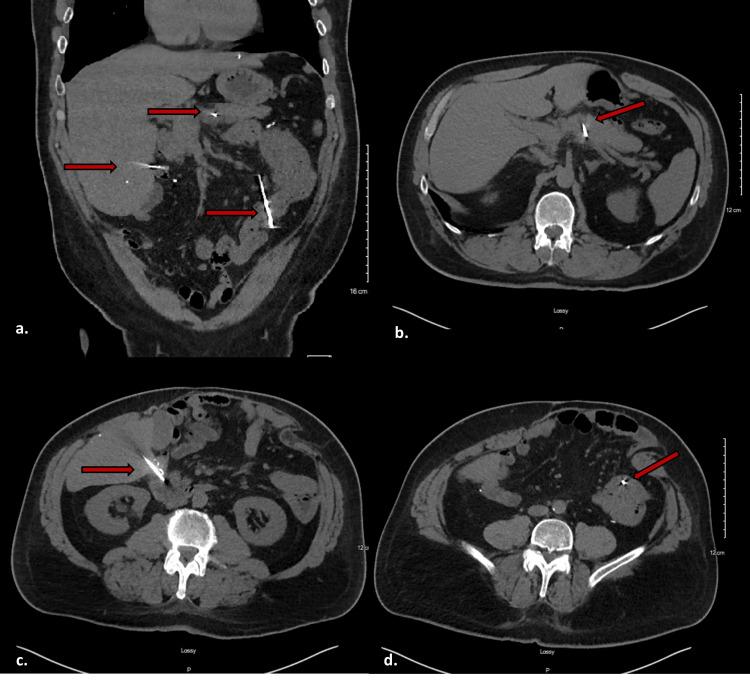

Penetrating abdominal trauma typically presents in an acute manner, and most require emergent intervention due to small bowel, large bowel, and liver injury. Here, we report a 53-year-old man who sustained multiple penetrating intra-abdominal injuries from a nail gun. The patient did not seek medical attention until four weeks after the incident. He presented with worsening abdominal pain and underwent exploratory laparotomy and removal of three intact nails. Fortunately, there were no injuries to the intra-abdominal organs, and the patient had an uneventful post-operative course and was seen in the office after hospital discharge in good condition.